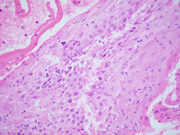

Figure 4. Cervical Pap test, Cell block, Hematoxylin-eosin, 200X magnification

Figure 5. Cervical Pap test, Cell block, Hematoxylin-eosin, 600X magnification

Figure 6. Cervical Pap test, Cell block, Hematoxylin-eosin, 600X magnification

On the ThinPrep, the cells are mostly seen in clusters or lying singly. They are large cells with well-defined moderate to abundant amounts of granular to vacuolated cytoplasm. The nuclear:cytoplasmic (N:C) ratio is variable and is focally increased. The nuclei are round to ovoid. The chromatin is mostly granular, the nuclear membranes are smooth to mildly irregular, and the nucleoli are prominent (Images 1-3). On the cell block section, decidua is seen in the form of flat sheets with round to polygonal epithelioid cells with well-defined eosinophilic cytoplasm. The nuclear characteristics are similar to that noted on the ThinPrep except that the chromatin is vesicular to granular (probably related to the differences in the stain) (Images 4-6).

The correct cytologic interpretation of decidua essentially relies on morphologic assessment and correlation with clinical history (as it is usually associated with the presence of excess progesterone).  A cell block preparation can also aid in the interpretation as it further highlights the architecture and the cellular details of decidua.